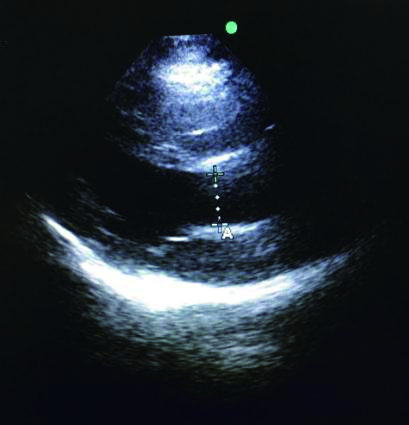

1.2.1 IJV/CCA截面积比值测量及计算方法患者取去枕平卧位,充分暴露颈部,选择甲状软骨最低位,将超声探头轻放于颈部血管处,分别测得头部正位时,双侧颈内静脉与颈总动脉横截面,冻结超声图像,使用电子标记界定颈内静脉和颈总动脉横截面的长径,同时,使用电子标记测得横截面周长,并且使用预先加载到超声单元中的程序计算颈部血管的横截面积,最后计算IJV/CCA截面积比值(图 1)。

| 图 1 超声电子标记的颈内静脉(A)和颈总动脉(B)周长 Figure 1 The perimeter of the internal jugular vein (A) and common carotid artery (B) electronic marked by ultrasound |